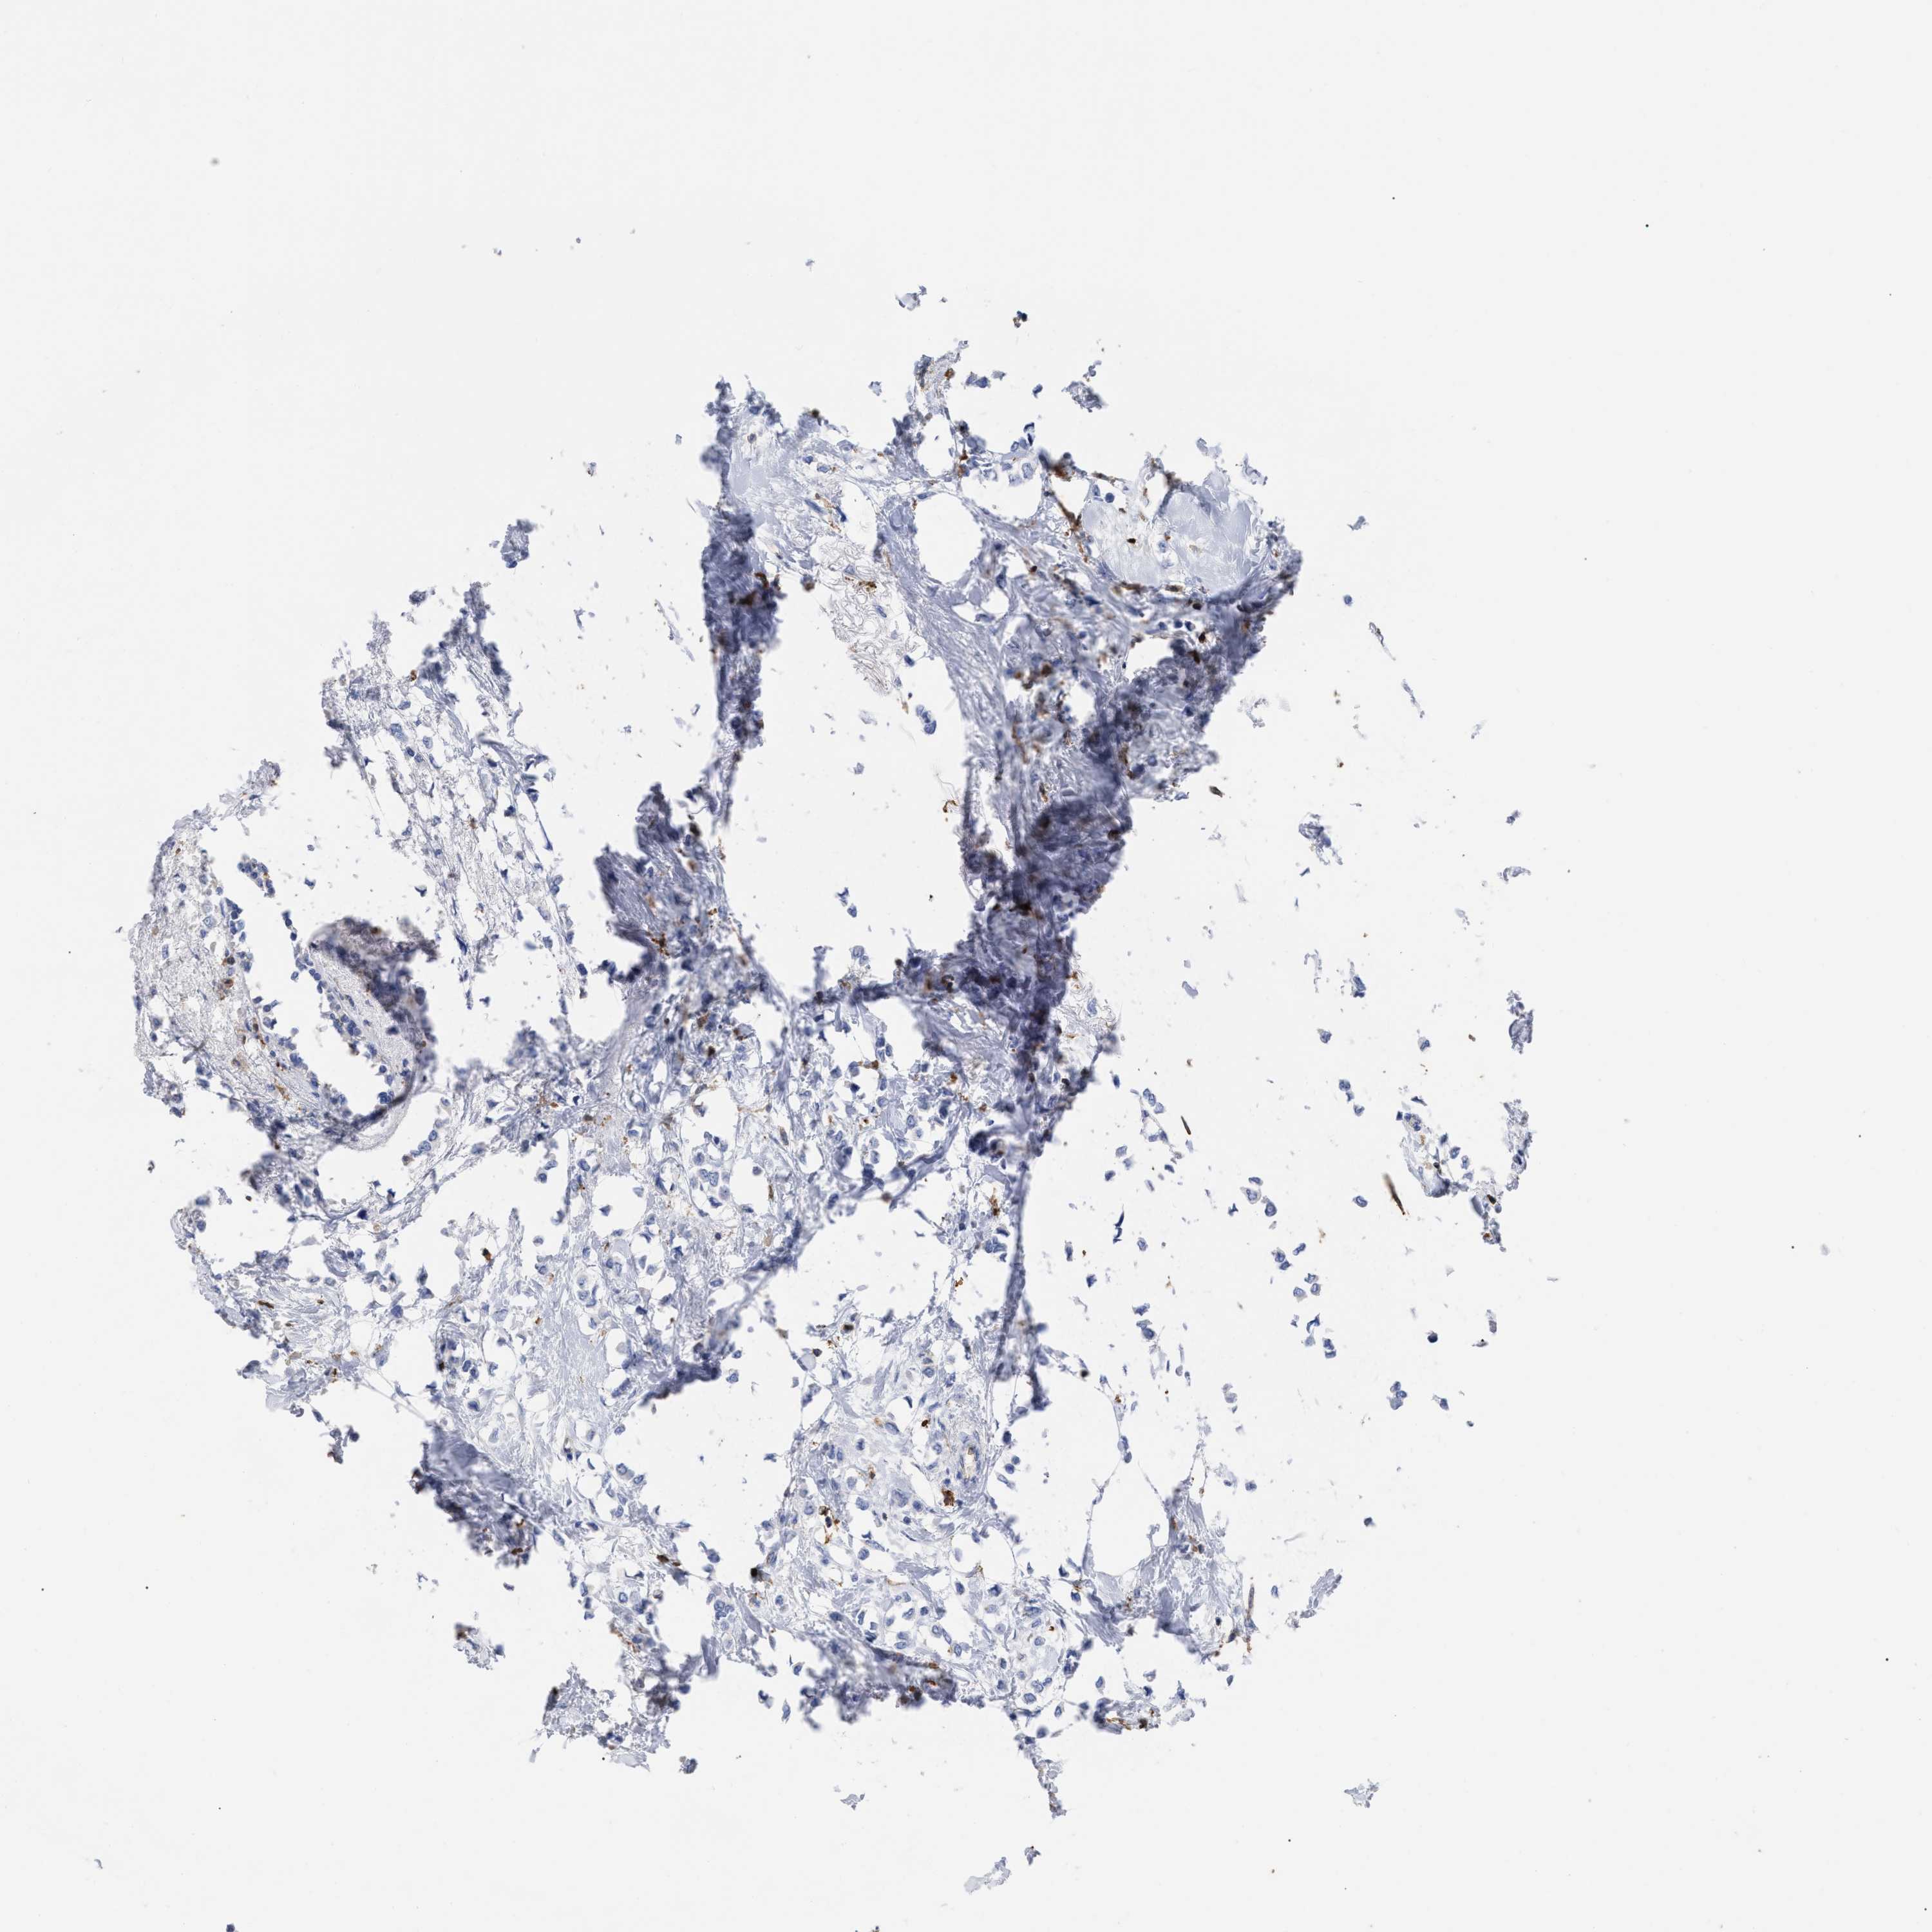

CANCER BREAST CANCER Show tissue menu

BRCA TCGA BRCA VALIDATION PROTEIN EXPRESSION